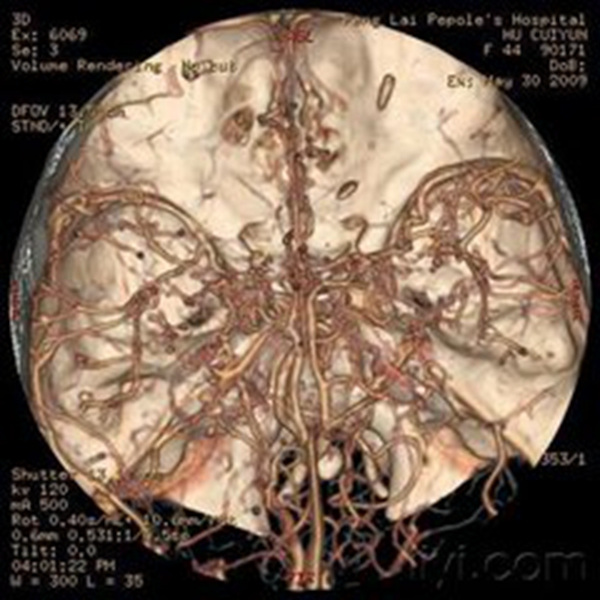

煙霧病造影表現

煙霧病造影圖

煙霧病造影

煙霧病遺傳的模式圖

煙霧病血管縮小

煙霧病血管造影